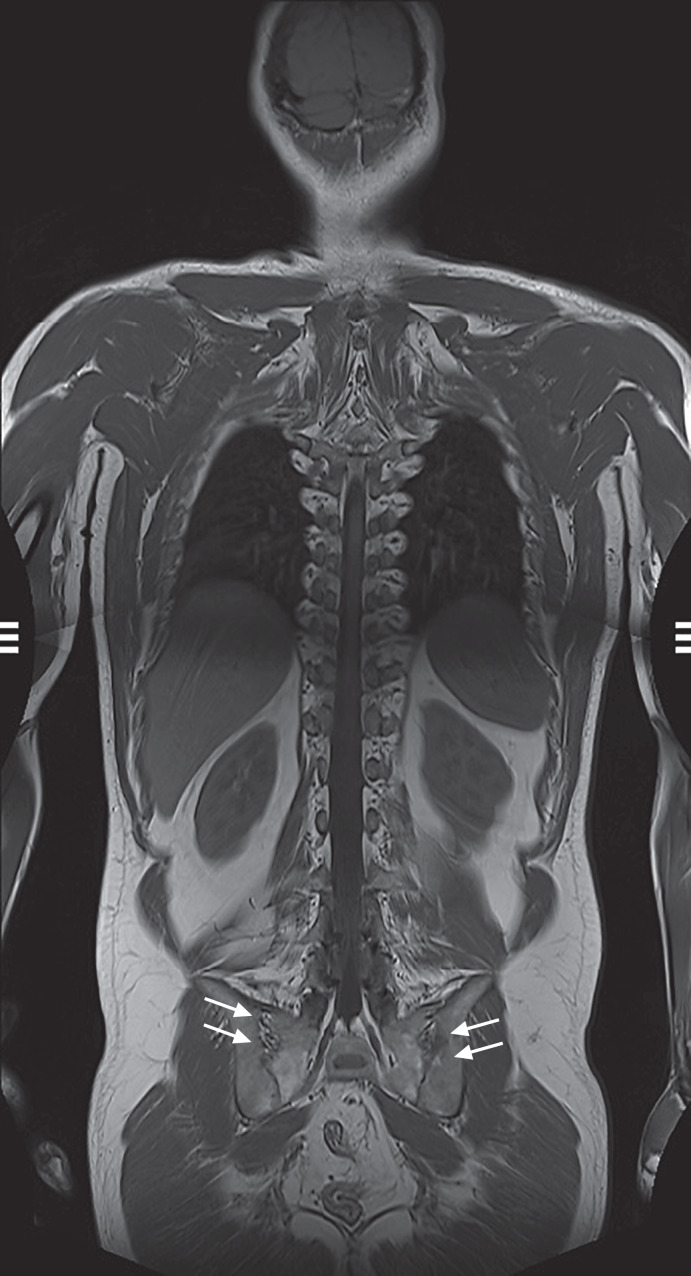

Case presentation: Our patient initially presented with axSpA at the age of 27. Nine years later, CD was diagnosed by the age of 36. One year after the diagnosis of CD, a spontaneous ileal perforation occurred as part of a disease course refractory to multiple anti-TNF antibodies and intolerance to immunomodulators. However, the axSpA showed a response to the anti-TNF certolizumab pegol. After stopping certolizumab pegol, we enrolled the patient into the M15-991 induction trial (MOTIVATE) and the maintenance trial (FORTIFY) testing the anti-IL-23 antibody risankizumab versus placebo in CD with failure to prior biological therapy. As a result, risankizumab induced a CD response but failed to control the axSpA. Considering the CD refractory and the axSpA responding to anti-TNFs, we initiated a DTT with risankizumab and certolizumab pegol. Risankizumab and certolizumab pegol together improved both CD and axSpA. As adverse events, there were only two episodes of spontaneously resolving common colds during the 19-month reviewed period.